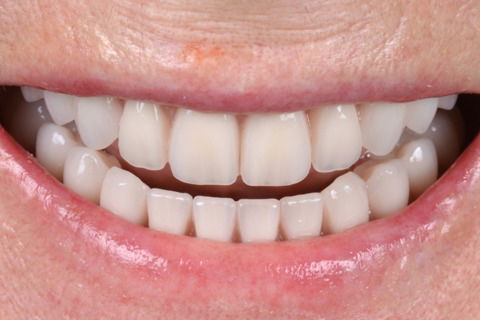

Sorriso final

Foto 17 Sorriso final